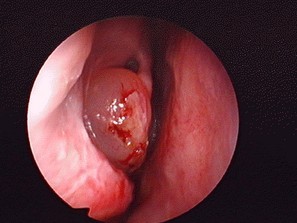

鼻息肉引發(fā)的癥狀是什么

1、鼻塞:鼻息肉引起的鼻塞往往是逐漸加重的雙側(cè)鼻塞。和鼻炎的鼻塞不同的是,鼻息肉引起的鼻塞是持續(xù)性的,應(yīng)用滴鼻藥物也只能部分緩解,沒多久又出現(xiàn)鼻塞。

2、鼻涕:鼻涕偶見,主要癥狀有多種性狀的鼻涕、黏膿樣的、稀白的鼻涕等等。主要是看有無炎癥并發(fā)。

3、嗅覺減退或消失:當(dāng)出現(xiàn)這個癥狀,說明已經(jīng)嚴(yán)重影響到鼻腔功能,此時多半伴有各類鼻炎的出現(xiàn)。

4、鼻息肉較巨大:可能有腫物從前鼻孔脫出或墜至口咽部;部分患者可有頭痛、頭暈癥狀:巨大鼻息肉還可引起面容改變——鼻背變寬、變成“蛙鼻”等。